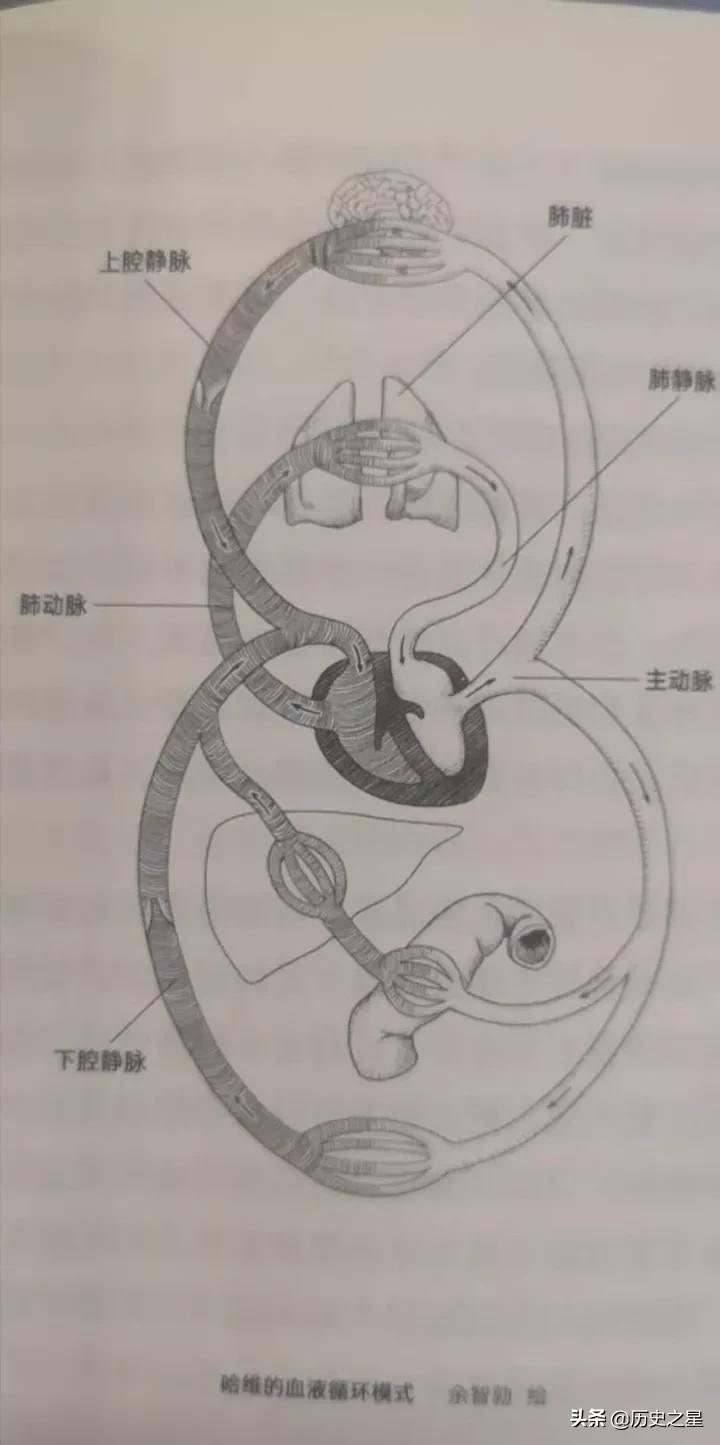

7、血液循环的发现——威廉•哈维(1578~1657)

英国内科医生威廉•哈维,经过9年的实验观察,证实了人体和动物的体内存在血液往复循环运动,于1628年发表了伟大著作《动物心血运动解剖论》。

哈维在书中指出,动脉把血液从心脏输出而同时静脉把血液输入心脏,心脏的功能就是把血液泵入动脉。哈维给出了大量的实验证据,严密地论证了他的学说。

《动物心血运动解剖论》是现代生理学的起点,使人们对人体自身的工作原理有一个基本的了解,对现代医学产生重大贡献。